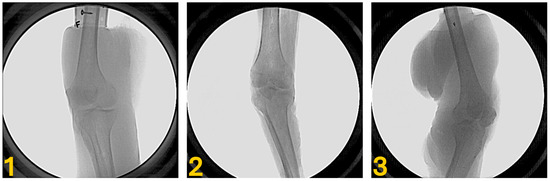

Modified Hofmann Articulated Spacer in the Treatment of Peri-Prosthetic Joint Infection of the Knee—Surgical Technique and Early Clinical Evaluation

Background/Objectives: The rate of periprosthetic joint infection (PJI) is expected to increase in the next years worldwide, mainly due to increasing volume of total joint replacement, longer prosthesis lifespans, and patients with multiple comorbidities. The aim of this study is to describe [...] Read more.

Background/Objectives: The rate of periprosthetic joint infection (PJI) is expected to increase in the next years worldwide, mainly due to increasing volume of total joint replacement, longer prosthesis lifespans, and patients with multiple comorbidities. The aim of this study is to describe our personal technique, the modified Hofmann Articulated Spacer (mHAS), in which a CR femoral shield and a partially threaded cannulated screw are inserted into the liner replicating a tibial stem, and to evaluate the efficacy of the spacer as a definitive treatment option in selected patients with knee infections. Methods: A consecutive series of 132 patients were treated for orthopedic infection at the Orthopedic and Trauma Center, University of Turin, between November 2023 and May 2025. All patients included in the study had undergone knee prosthesis removal followed by the implantation of a modified Hofmann Articulated Spacer (mHAS). Functional recovery was evaluated through clinical examination, particularly knee range of motion, and patient-reported outcome measures (PROMs), including the Knee Society Score (KSS), Oxford Knee Score (OKS), and the EQ-5D-5L Visual Analogue Scale (VAS). Results: Nine patients were enrolled in the study, at a mean follow-up of 8.12 months (range: 3–13). The mean range of motion of the knee was 95 degrees (range: 80–120°, SD: 15°). The Knee Society Score (KSS) presented a mean value of 71.9 (SD: 18.11). The Oxford Knee Score (OKS) showed a mean value of 30.8 (SD: 8.5). The EuroQol-5 Dimension-5 Level Visual Analogue Scale (EQ-5D-5L VAS) scores demonstrated an excellent quality of life among the participants. Conclusions: The Modified Hofmann Articulated Spacer demonstrated good functional, qualitative outcomes and eradication rates in patients who underwent the first-stage revision TKA for PKI. This has led us to propose it as a definitive treatment option for more critical and low-demand patients and to postpone the second-stage surgery in the remaining cohort due to satisfactory spacer joint function without pain. Full article